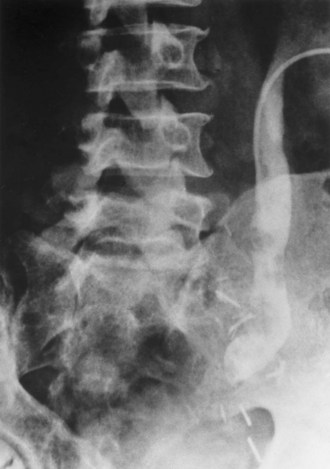

Although intravenous pyelography has been the traditional means for diagnosis of upper tract lesions, computed tomographic (CT) urography is increasingly performed today. CT is easier to perform and less labor intensive than intravenous pyelography. It also has a higher degree of accuracy in determining the presence of renal parenchymal lesions. On the other hand, small urinary filling defects (<5 mm) may be missed between the “cuts” of the traditional CT scan. More recently, CT urography has been performed to obtain a three-dimensional image of the upper tracts. This technique appears to be equal to intravenous pyelography in imaging the ureters and renal pelvis (McTavish et al, 2002). With CT urography, the sensitivity for detecting upper tract malignant disease has been reported to approach 100%, with a specificity of 60% and a negative predictive value of 100% (Caoili et al, 2002). CT urography does, however, expose the patient to higher doses of radiation.

Radiolucent filling defects, obstruction or incomplete filling of a part of the upper tract, and nonvisualization of the collecting system are the typical findings suggestive of an upper urinary tract tumor. Filling defects, which account for 50% to 75% of cases, typically require the intravenous administration of contrast material to be identified (Murphy et al, 1981; Fein and McClennan, 1986). The differential diagnosis of these defects includes blood clot, stones, overlying bowel gas, external compression, sloughed papilla, and fungus ball. Stones can be ruled out most easily by confirmation of calcification by renal ultrasonography or CT. TCCs have an average density of 46 Hounsfield units (HU) and a range of 10 to 70 HU (Lantz and Hattery, 1984). This is in contrast to an average of 100 HU seen in radiolucent uric acid stones (range, 80 to 250 HU). Thus CT can be useful in distinguishing between these two common causes of radiolucent filling defect on excretory urography or retrograde ureterography. The impact of hydronephrosis and nonvisualization for renal pelvis tumors versus ureteral tumors as indicators of a higher stage is uncertain. Nonvisualization is reported in 20% of renal pelvis tumors, only 33% of which are invasive (McCarron et al, 1983). Nonvisualization is reported in 37% to 45% of ureteral tumors and carried a 60% risk of invasion in one series (McCarron et al, 1983). In other reports there is no correlation of nonvisualization and stage (Batata and Grabstald, 1976; Anderstrom et al, 1989). Hydronephrosis with or without an associated filling defect is linked with invasion in 80% of ureteral tumors (McCarron et al, 1983; Cho et al, 2007).

Radiolucent, noncalcified lesions may require additional evaluation by retrograde urography or ureteroscopy, with or without biopsy and cytology. Overall, retrograde urography has an accuracy of 75% in diagnosis of an upper tract malignant neoplasm (Murphy et al, 1981). An incompletely filled or obstructed renal infundibulum or calyx, occurring in 10% to 30% of cases, again typically requires retrograde urography or ureteroscopy to confirm the diagnosis. Obstruction of the urinary tract is a poor prognostic sign for tumor invasion (Babaian and Johnson, 1980).